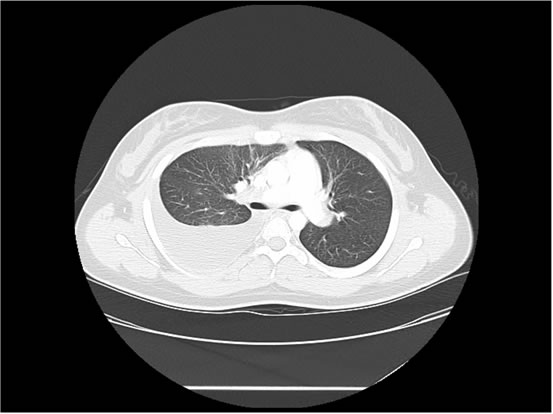

We ordered a CT scan with infusion of the chest

I will show you 12 CT-scan cuts.